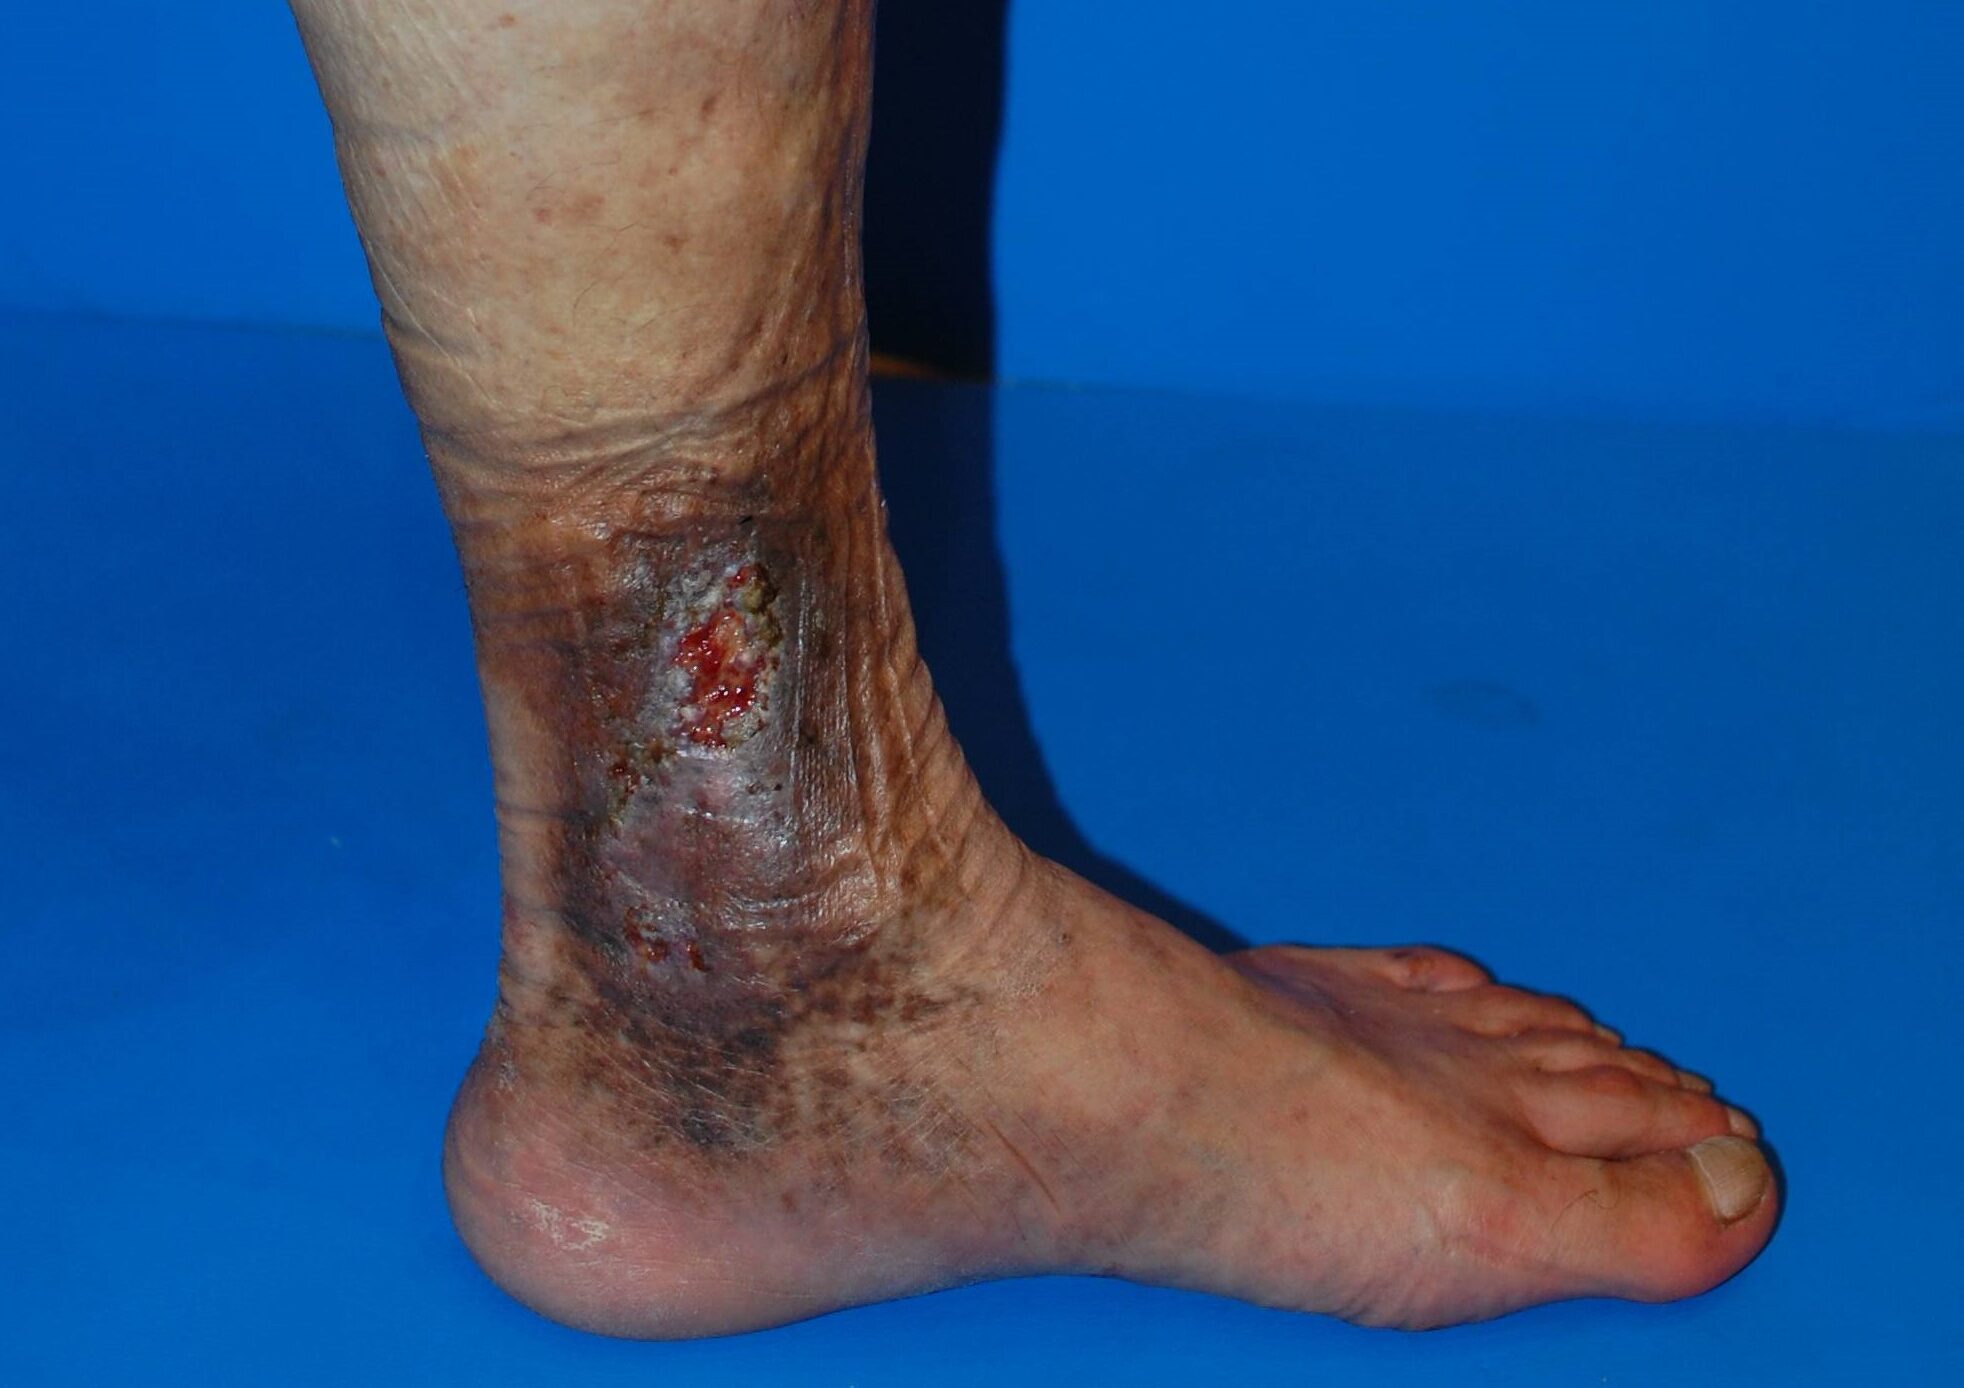

足首まわりに色素沈着や湿疹がある

下肢静脈瘤が進行すると、足首周囲に茶色っぽい色素沈着が出たり、

湿疹やかゆみ、うっ滞性皮膚炎を伴ったりすることがあります。

この段階になると、見た目の問題だけではなく皮膚トラブルも起こっている可能性があります。

うっ滞性皮膚炎 画像

色素沈着

足首まわりが茶色くくすんだように見える場合、静脈うっ滞の影響で皮膚に変化が起きている可能性があります。

湿疹・かゆみ・うっ滞性皮膚炎

皮膚の状態が悪くなり、かゆみや赤み、湿疹が出ることがあります。

皮膚科で軟膏を使っても改善が不十分な場合、背景に下肢静脈瘤があることもあります。

皮膚潰瘍

さらに進行すると、皮膚が傷つきやすくなり、治りにくい潰瘍ができることがあります。

ここまで進行する前に治療を検討することが大切です。